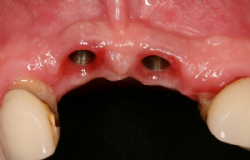

Abbildung 3: Astra-Implantate am Ende der Einheilphase